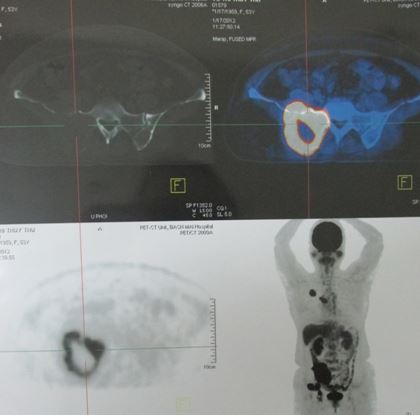

+ Bệnh nhân được chỉ định PET/CT

Hình 3,4,5: Hình ảnh PET/CT u phổi P kích thước 3,4cm tăng hấp thu FDG, max SUV là 7,8, di căn xương cột sống, xương chậu trái max SUV là 8,4.